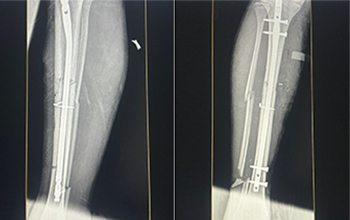

At CZMEDITECH, we are dedicated to providing reliable orthopedic solutions through real clinical success. Each surgical case reflects our continuous innovation in spinal fixation, trauma management, joint reconstruction, maxillofacial repair, and veterinary orthopedics. By integrating advanced manufacturing technology with the expertise of experienced surgeons, we ensure every implant delivers safety, precision, and long-term recovery.

Explore below a selection of clinical cases that demonstrate how our CE-certified implants help restore mobility, stability, and confidence in patients worldwide.